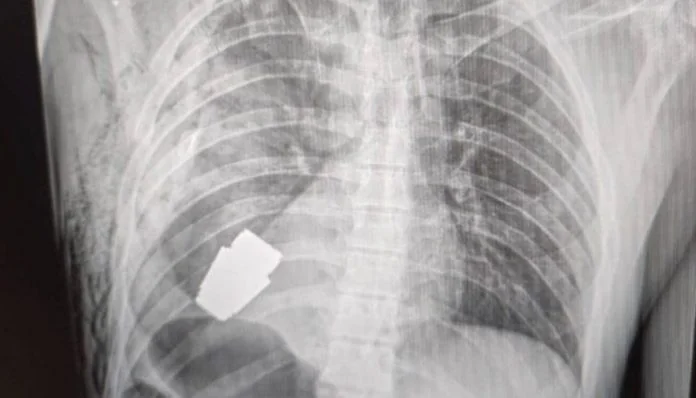

Hirurzi su uklonili eksplozivno sredstvo koje se nalazilo tik ispod srca ozlijeđenog vojnika, dok su se dva sapera pobrinula da operacija bude provedena sigurno, kazala je Hanna Maliar, zamjenica ukrajinskog ministra odbrane, koja je objavila fotografiju na kojoj se vidi rendgenska snimka granate u tijelu vojnika.

– Vojni doktori su izveli su operaciju uklanjanja VOG granate, koja se nije raspala, iz tijela vojnika – napisala je u objavi na Facebooku.

Anton Geraščenko, savjetnik ukrajinskog ministra unutrašnjih poslova, rekao je da je tim sapera neutralizirao streljivo i opisao postupak kao onaj koji će “ući u medicinske udžbenike”.

– Operacija je izvedena bez korištenja elektrokoagulacije – uobičajene metode za kontrolu krvarenja tokom operacije – jer bi “granata mogla detonirati u svakom trenutku – rekao je Maliar.

Geraščenko je rano u četvrtak na Telegrama napisao kako je neeksplodirani dio granate izvađen ispod srca.

– Granata nije eksplodirala, ali je ostala eksplozivna – kazao je.

Hirurzi su uklonili eksplozivno sredstvo koje se nalazilo tik ispod srca ozlijeđenog vojnika, dok su se dva sapera pobrinula da operacija bude provedena sigurno, kazala je Hanna Maliar, zamjenica ukrajinskog ministra odbrane, koja je objavila fotografiju na kojoj se vidi rendgenska snimka granate u tijelu vojnika.

– Vojni doktori su izveli su operaciju uklanjanja VOG granate, koja se nije raspala, iz tijela vojnika – napisala je u objavi na Facebooku.

Anton Geraščenko, savjetnik ukrajinskog ministra unutrašnjih poslova, rekao je da je tim sapera neutralizirao streljivo i opisao postupak kao onaj koji će “ući u medicinske udžbenike”.

– Operacija je izvedena bez korištenja elektrokoagulacije – uobičajene metode za kontrolu krvarenja tokom operacije – jer bi “granata mogla detonirati u svakom trenutku – rekao je Maliar.

Geraščenko je rano u četvrtak na Telegrama napisao kako je neeksplodirani dio granate izvađen ispod srca.

– Granata nije eksplodirala, ali je ostala eksplozivna – kazao je.